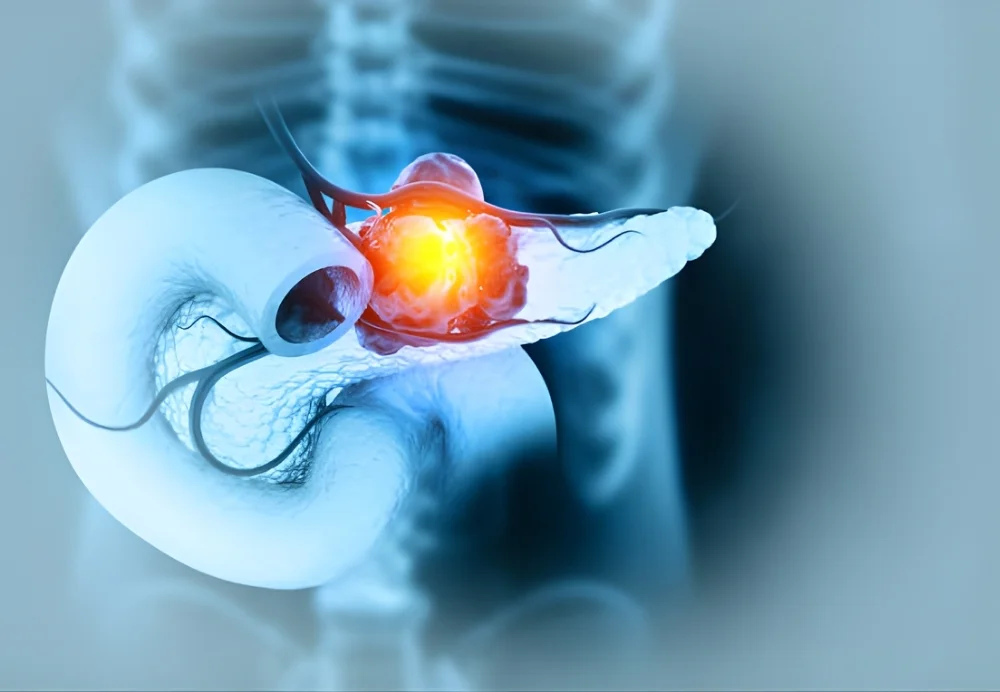

TYPES OF PANCREAS CANCER

Pancreas cancer is not a single disease. Different types have distinct behavior and treatment approaches.

Adenocarcinoma

Most common type, arising from ductal cells; usually treated with surgery and chemotherapy.

Neuroendocrine tumors

Rare, slow-growing tumors from hormone-producing cells; treatment depends on size, location, and spread.

Acinar cell carcinoma

Uncommon, develops from enzyme-producing cells; management is tailored individually.